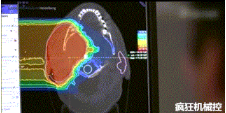

光柵掃描被集成到360°重離子治療一體機(jī)中,這種極其精確的照射方法以毫米為單位掃描腫瘤,可以保護(hù)健康組織且只治療腫瘤區(qū)域。

特別是腫瘤在高度輻射敏感位置或者諸如視神經(jīng)附近的復(fù)雜位置,可以通過選擇最佳射束入射角來減小這些器官的損傷。